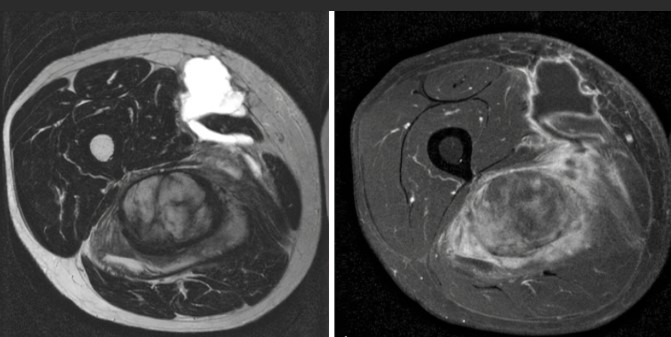

Abbildung zeigt Bilder einer MRT bei Krebs: (1) Wirbelsäulentumor, (2) Knochentumor, (3) Spinalkanaltumor, (4) Mamma-CA (Brustkrebs)

Tumorgewebe ändert die Eigenschaften des betroffenen Gewebes oder wenn es sich um gestreute Tumormetastasen handelt, stellt es sich als Fremdkörpergewebe dar mit anderen Eigenschaften als die Umgebung, die MRT stellt dies technisch als Bildveränderung sichtbar dar und lässt sich somit als Tumor diagnostizieren. Bei zusätzlichen Kontrastmittel-gestützten Bildsequenzen lässt sich zudem das abnormale Durchblutungsverhalten der Tumore erkennen: Das Kontrastmittel ist selbst deutlich als verändertes Signal der Gewebe wahrzunehmen. Tumore können entweder als zeitweise Verstärkung oder Verminderung des Bildsignals im Vergleich zum umgebenden Gewebe abgegrenzt werden.